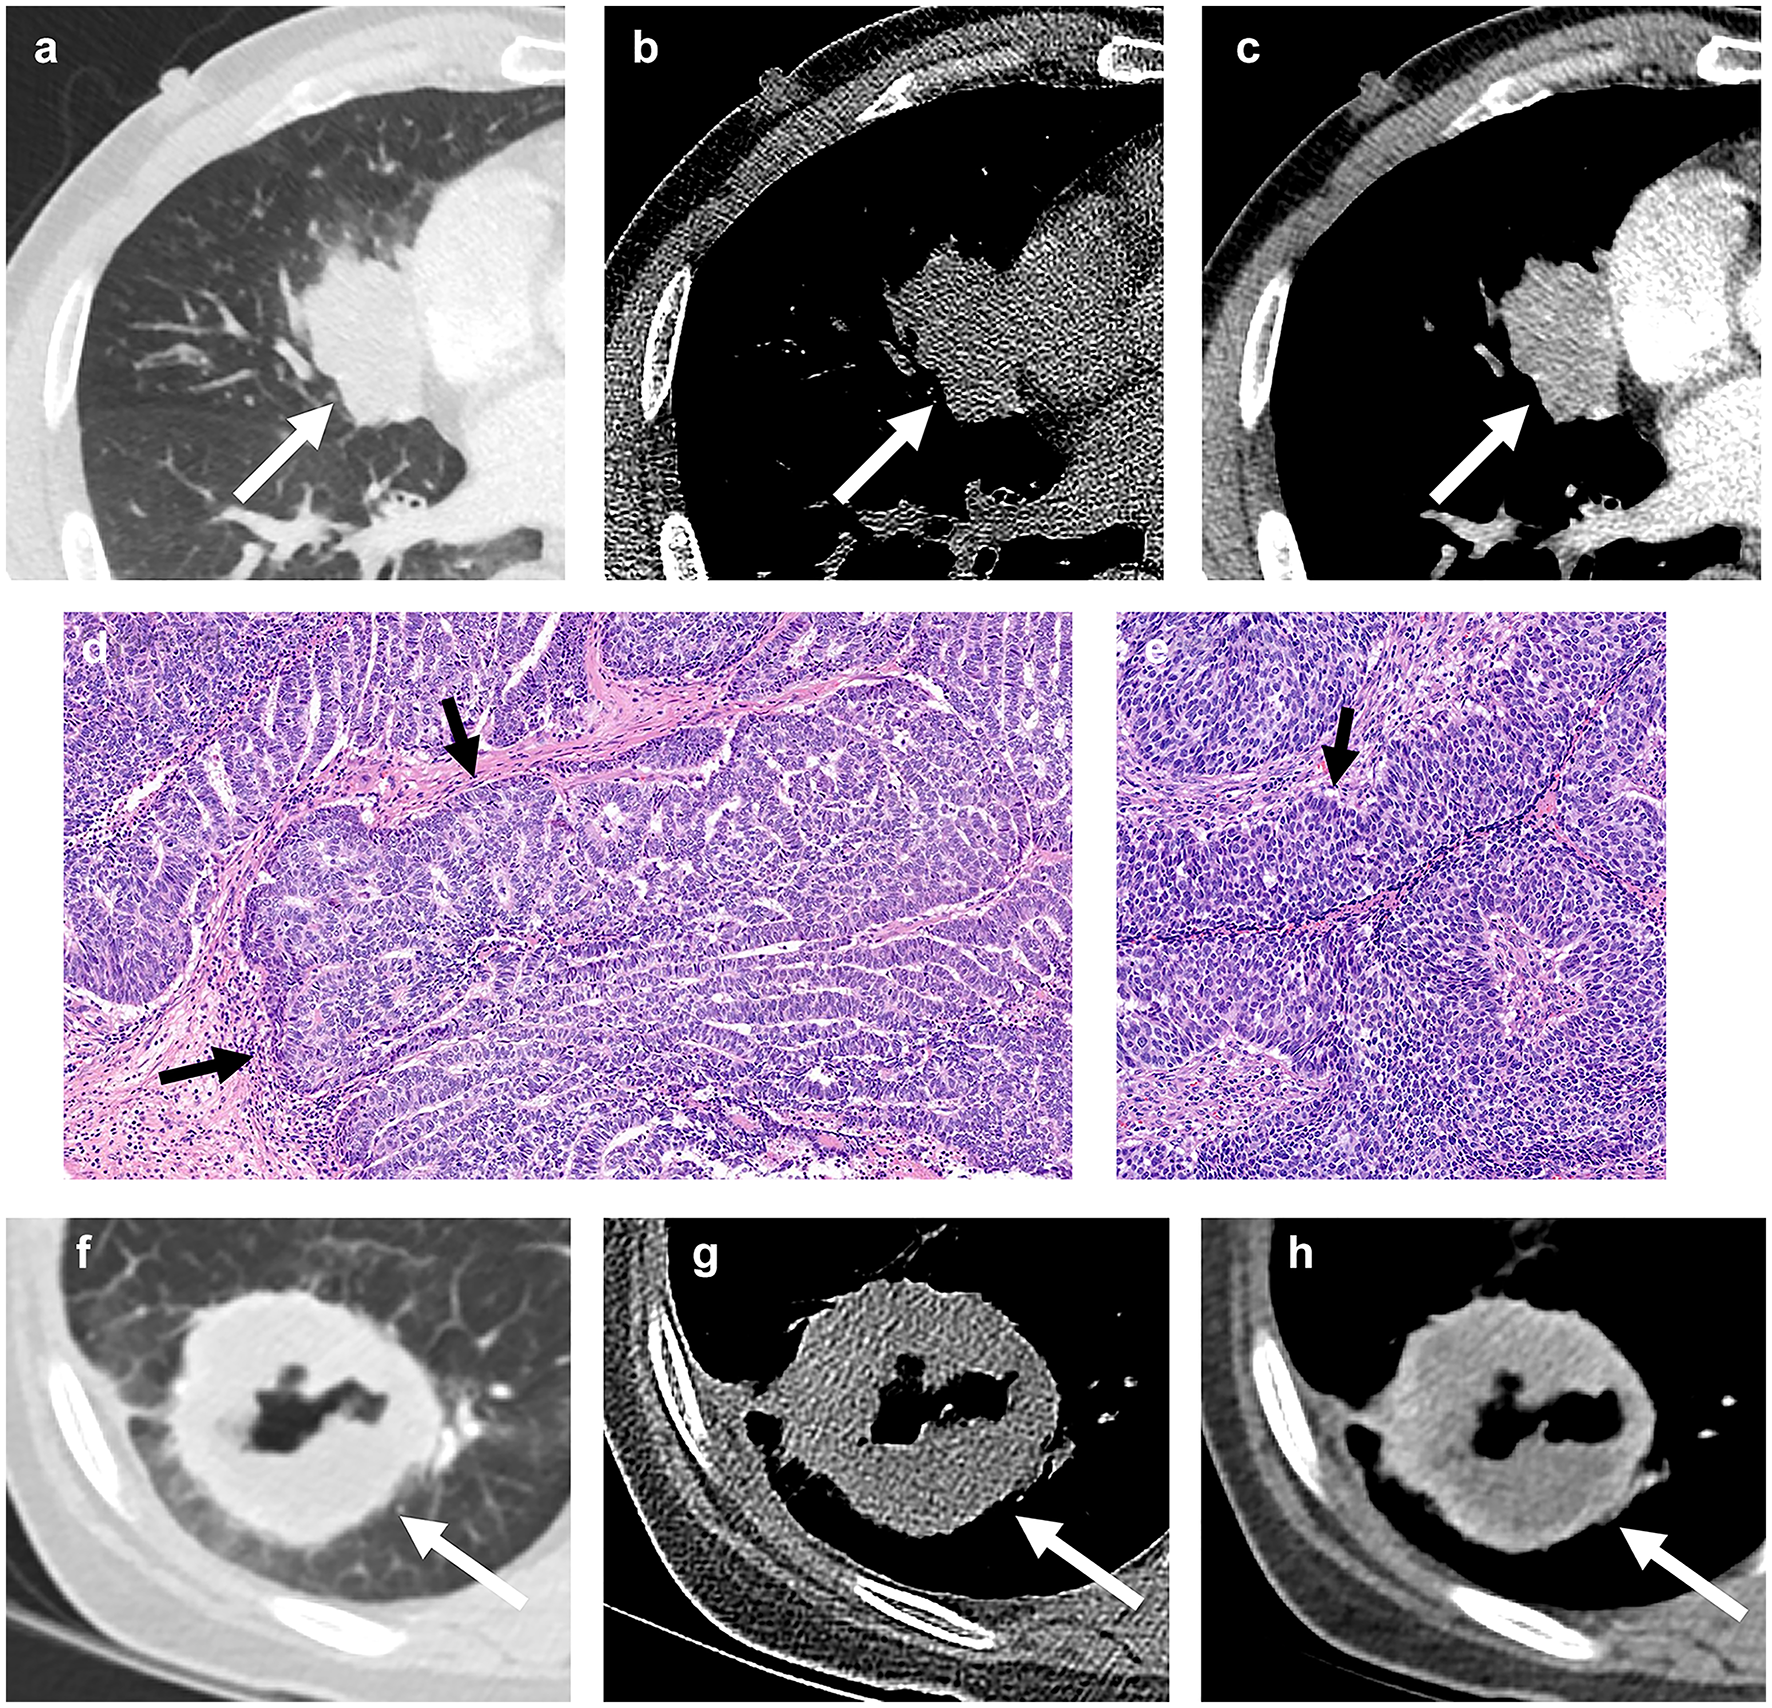

Fig. 2

A 60-year-old man with basaloid squamous cell carcinoma of lung. (a) A lung window setting computed tomography (CT) scan showing a lobulated mass (arrow) in right middle lobe. (b) and (c) Unenhanced (b) and enhanced (c) scans showing mild enhancement of the mass (arrows). (d) and (e) Photomicrograph images obtained at medium power magnification (haematoxylin and eosin stain) showing nests of tumor cells with peripheral palisading (arrow). A 67-year-old woman with non-basaloid squamous cell carcinoma of the lung. (f) A lung window setting CT showing a mass with cavitation (arrow) in the right lower lobe. (g) and (h) Unenhanced (g) and enhanced CT (h) showing cavitation and internal profuse necrosis.